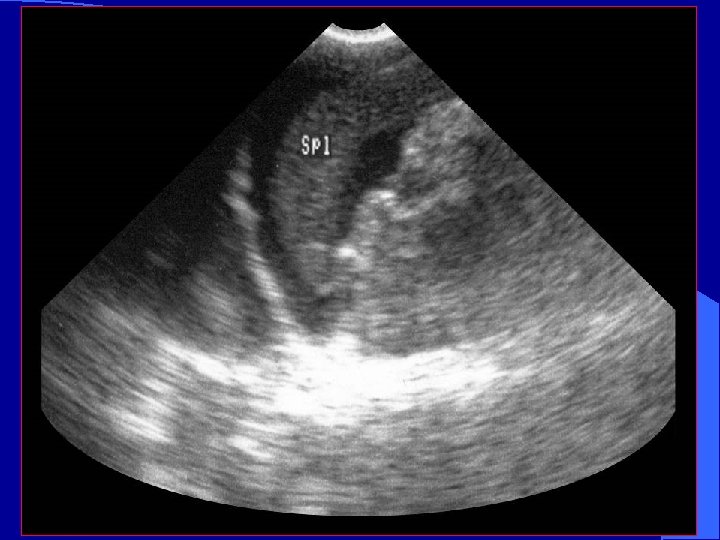

LUQ Scan Plane l More difficult – Acoustic window (spleen) is smaller than liver – Mild inspiration will optimize image – Bowel interference is common

LUQ Scan spleen * * * kidney * *Splenorenal fossa – a potential space

Normal Spleno -renal view Free fluid around spleen